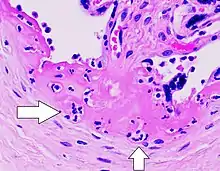

Villitis of unknown etiology (VUE), also known as chronic villitis, is a placental injury. VUE is an inflammatory condition involving the chorionic villi (placental villi). VUE is a recurrent condition and can be associated with intrauterine growth restriction (IUGR). IUGR involves the poor growth of the foetus, stillbirth, miscarriage, and premature delivery.[3][4] VUE recurs in about 1/3 of subsequent pregnancies.[5]

VUE is a common lesion characterised by inflammation in the placental chorionic villi. VUE is also characterised by the transfer of maternal lymphocytes across the placenta.[4]

VUE is diagnosed in 7–10% placentas in pregnancies. Roughly 80% of the VUE cases are in term placentas (greater than 37 weeks of pregnancy). A case of VUE in a placenta less than 32 weeks old should be screened for infectious villitis.[3]